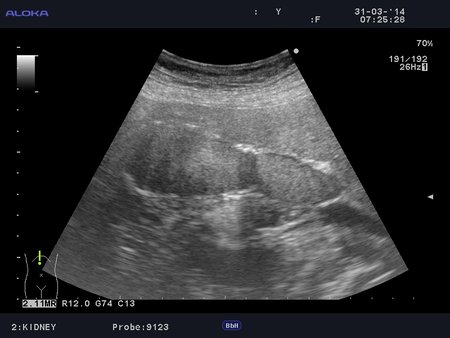

Фарфоровый желчный пузырь (Porcelain gallbladder)

Женщина средних лет без жалоб на здоровье.

Еще случай.

Бабушка из отделения сестринского ухода, без жалоб на боли в животе. Лаб. анализы не изменены.

Если кальциноз стенки полный и содержимое пузыря осмотру не доступно, то есть показания к проведению КТ-МРТ. Если стенки инкрустированы частично (как в представленных случаях) и можно оценить характер содержимого и структуру стенок, то можно ограничиться только УЗИ. Далее, если есть подозрение на опухоль то пациента направляют к онкологу, а он сам определяет дальнейшую тактику.